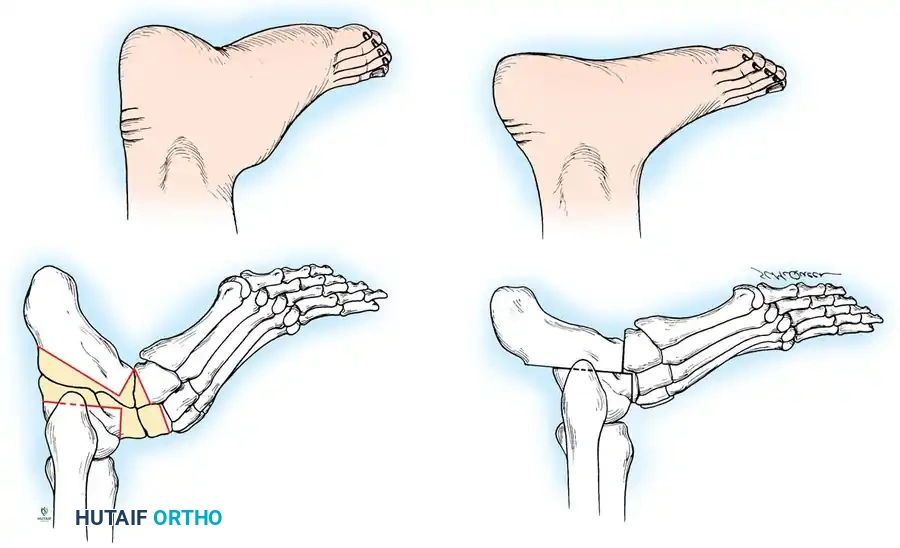

Fig. 1: A, Mild cavus deformity and clawing of toes. B, Calluses beneath metatarsal heads are the most common symptom prompting orthopaedic consultation. C, Marked forefoot equinus and resulting dorsal prominence of the tarsus. D, Forefoot is pronated in relation to the hindfoot during weight bearing. E, Shortening of the medial column of the foot.

Fig. 3: Lateral and frontal view of a rigidly plantar flexed first ray, the hallmark of Charcot-Marie-Tooth disease.

Fig. 4: The "Kickstand Effect." When the rigidly plantar flexed first ray strikes the ground, the heel is mechanically forced into varus.

Fig. 5: Eighteen-year-old man with CMT demonstrating fixed hindfoot varus, marked forefoot equinus, tight plantar fascia, and contracted Achilles tendon.